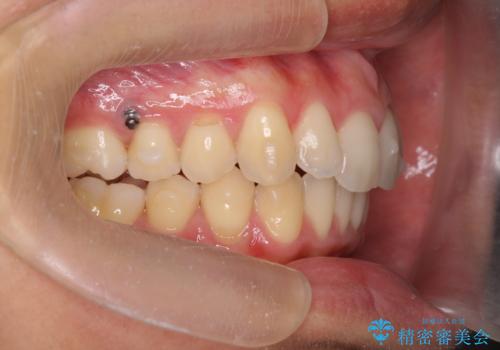

過蓋咬合・上顎前突・叢生を改善するマウスピース矯正

- 前歯のがたつき、不揃いさの改善を求めて来院されました。

・前歯の深い噛み合わせ (過蓋咬合)

・上顎前突(Angle Class2)

・叢生(がたつき)

以上のような問題点をマウスピース矯正インビザラインとマイクロインプラントを用いて矯正治療を行い改善して行きます。

20時間以上のマウスピース装着、ゴムかけを遵守していただいたおかげでしっかりと噛み合わせ、がたつきの改善を行うことができました。